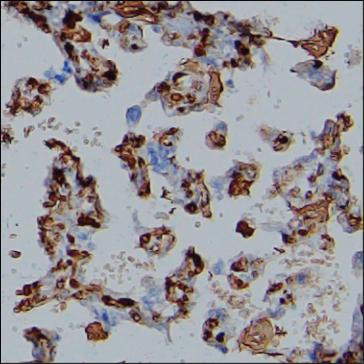

Produktinformationen "Anti-FGA"

Protein function: Cleaved by the protease thrombin to yield monomers which, together with fibrinogen beta (FGB) and fibrinogen gamma (FGG), polymerize to form an insoluble fibrin matrix. Fibrin has a major function in hemostasis as one of the primary components of blood clots. In addition, functions during the early stages of wound repair to stabilize the lesion and guide cell migration during re- epithelialization. Was originally thought to be essential for platelet aggregation, based on in vitro studies using anticoagulated blood. However, subsequent studies have shown that it is not absolutely required for thrombus formation in vivo. Enhances expression of SELP in activated platelets via an ITGB3-dependent pathway. Maternal fibrinogen is essential for successful pregnancy. Fibrin deposition is also associated with infection, where it protects against IFNG-mediated hemorrhage. May also facilitate the immune response via both innate and T-cell mediated pathways. [The UniProt Consortium]

| Schlagworte: | Anti-Fibrinogen alpha chain [Cleaved into: Fibrinopeptide A, Anti-Fibrinogen alpha chain], FGA Antibody |

| Hersteller: | Absea |

| Hersteller-Nr: | KC-195 |

| Antikörper-Typ: | Monoclonal |

| Klon: | KT9 |

| Konjugat: | No |

| Wirt: | Rat |

| Spezies-Reaktivität: | human |

| Immunogen: | Fibrinogen purified from human blood containing alpha,beta and gamma chains |